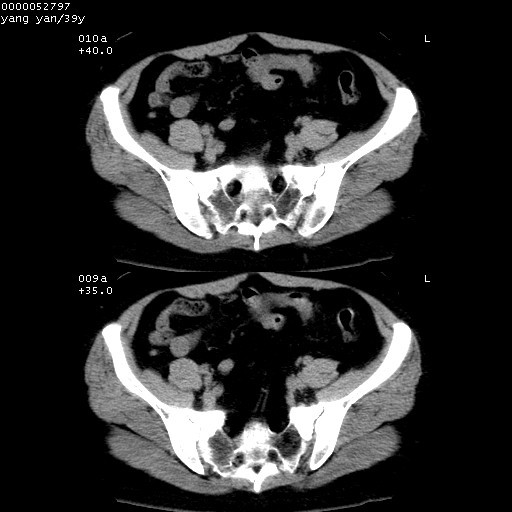

患者 女,39岁。因外伤检查,偶然发现。

典型!双侧骶髂关节致密性骨炎。

典型!病变主要累及双侧髂骨。常见于育龄期妇女。

致密性骨炎,一般不跨越关节面,可是这个骶骨关节面也有硬化。

髂骨致密性骨炎系一种以骨质硬化为特点的非特异性炎症,有高度致密的骨硬化现象,尤其以髂骨下2/3更为明显,但关节间隙则无改变。因位于骶髂关节,且该关节症状明显,故又称之为“骶髂关节致密性骨炎”。 本病90%以上为中年女性,以妊娠后期、尤其分娩后为多见,亦可见于尿路或女性附件慢性感染后,或盆腔内其他感染。此外,臀骶部的外伤亦可诱发或引起本病。  妊娠、分娩及外伤均可引起骶髂关节韧带的撕裂而易使局部的血供受阻。因此早期局部呈现充血、水肿及渗出增加等,渐而局部出现增生与变性反应,随着胶原纤维的致密化而向硬化演变;血管形成厚壁血管,易闭塞而引起髂骨耳状面处缺血和缺氧,骨质呈现硬化性改变,以致手术时局部出血较少。骶髂关节囊壁显示纤维增生、弹性降低及松动样改变。继发于盆腔内炎症者亦出现相类似的病理改变,可能系细菌内毒素作用所致。